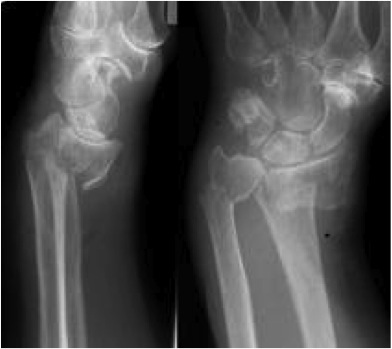

Wrist fractures